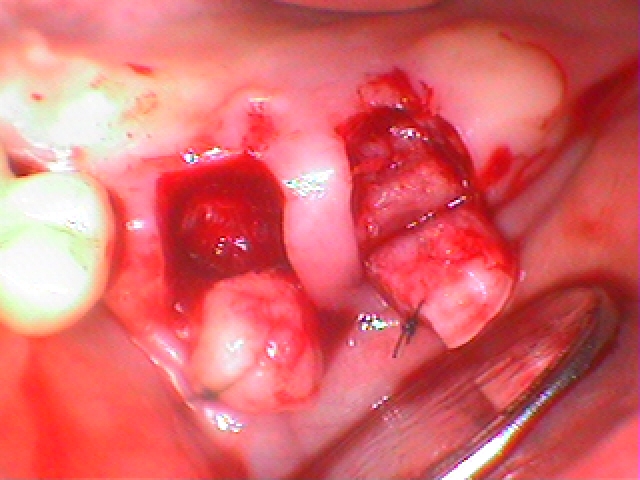

右上6,7番にインプラント2本を追加で埋入していきました